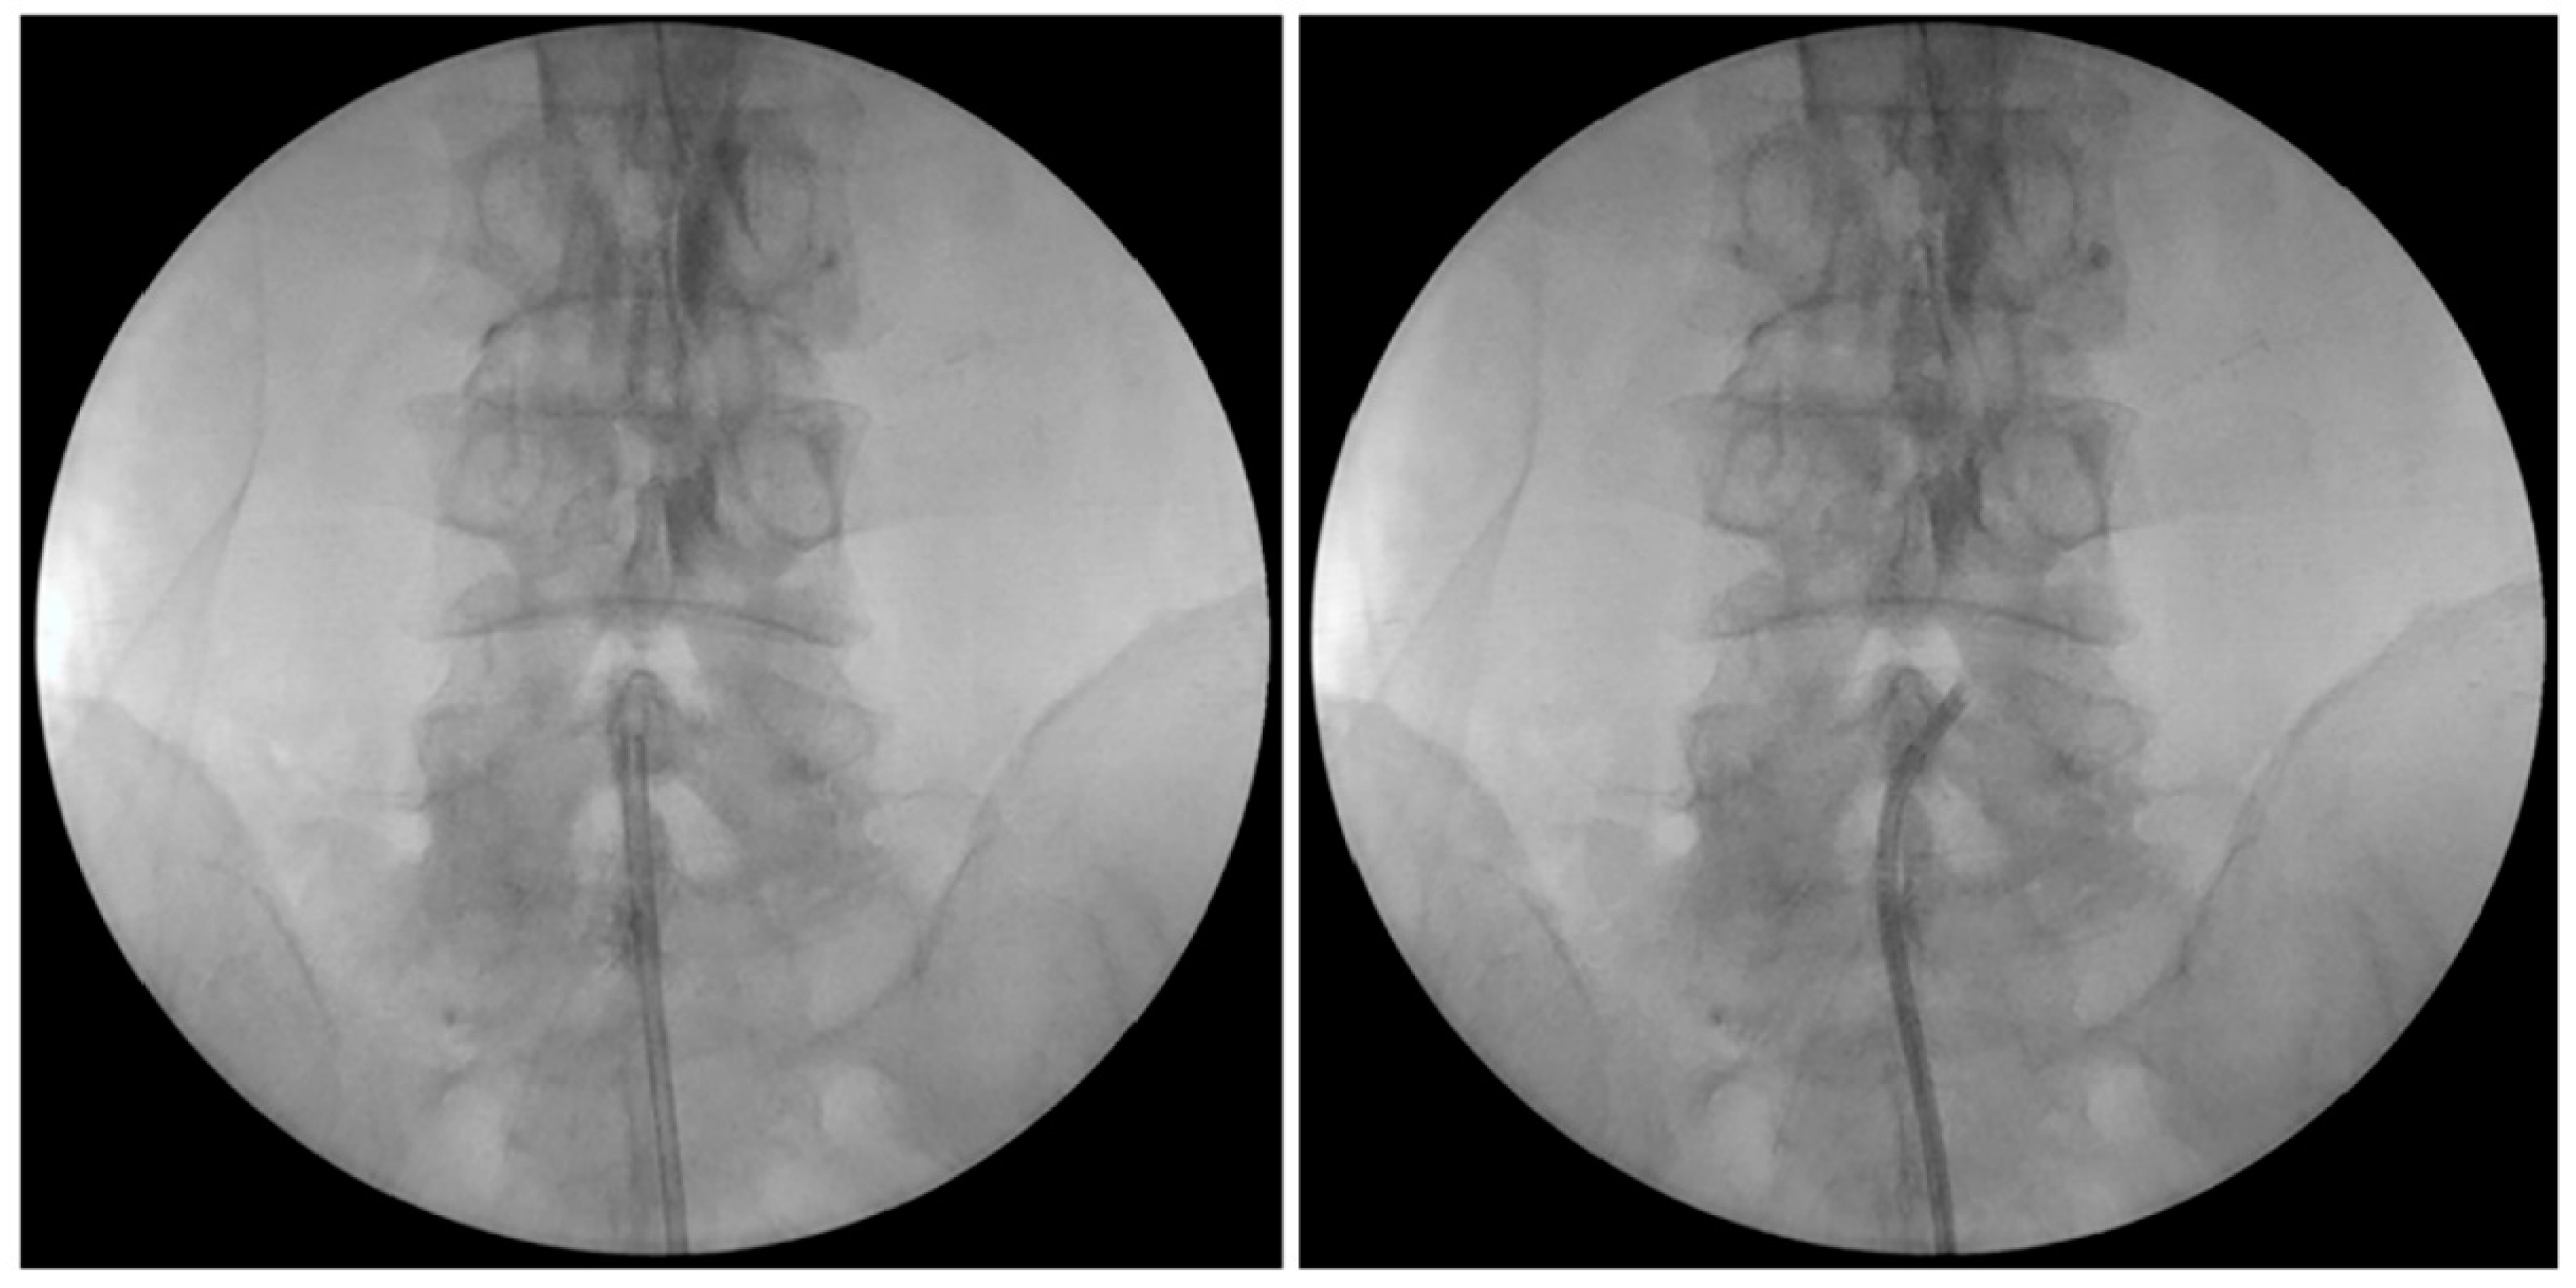

2.5. PEN with Steering Catheter